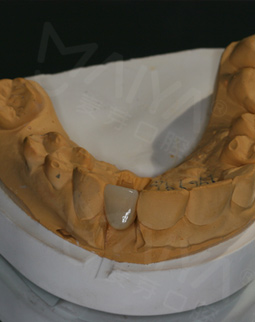

今天又来复诊,愈合基台无松动,可以戴牙冠了,取模也很方便,然后还有比色,一颗种植牙看着只是种牙而已,其实每个环节还是挺细心的,这次复诊刚好碰上活动,在此祝福生日快乐,也希望更多的缺牙人能在这里重拾口福健康!

2017年3月 这里有最好的医生

戴完牙冠,无论是颜色还是咀嚼性能方面都和我的真牙一样,恢复了往日的形象也恢复了原有的咀嚼功能。种植牙手术的成功,让我拥有了更加灿烂的笑容。十年里我从来没有在中国去过任何医院看过任何医生,但是这次却在麦芽口腔见识了中国医生,和中国功夫一样,very good!这里有最棒的环境,而且这里有最好的医生!